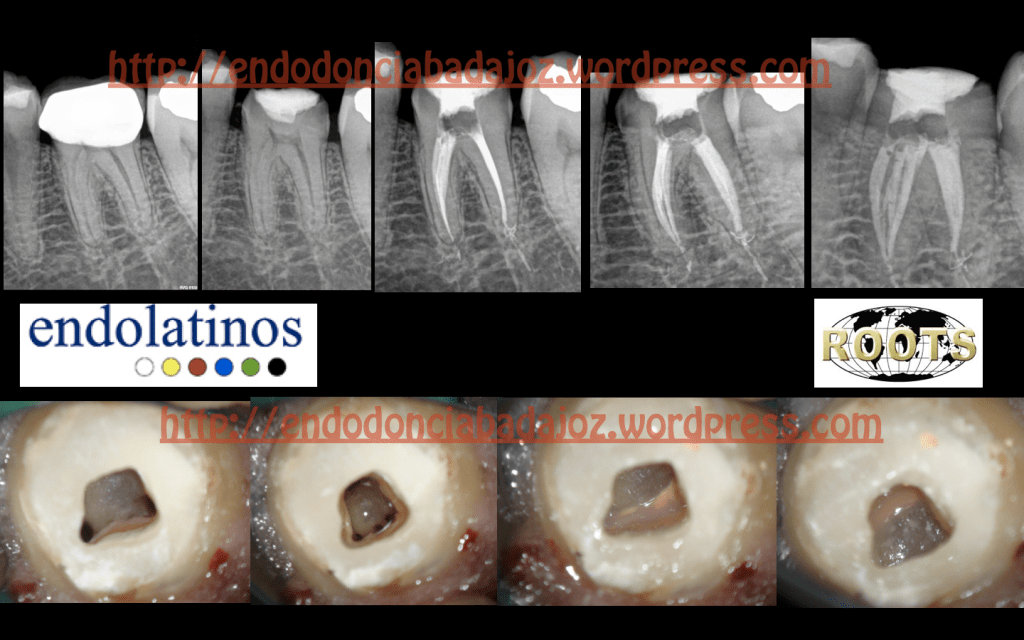

Pulpitis Irreversible de la pieza 3.6, Instrumentada con Mtwo hasta una conicidad de 25/ 6% (Itsmo Mesial instrumentado hasta un 20/6%). Obturado con condensación Vertical con ola continua. Se han sellado las entradas de los conductos con composite fluido para evitar una filtración coronal. Un saludo